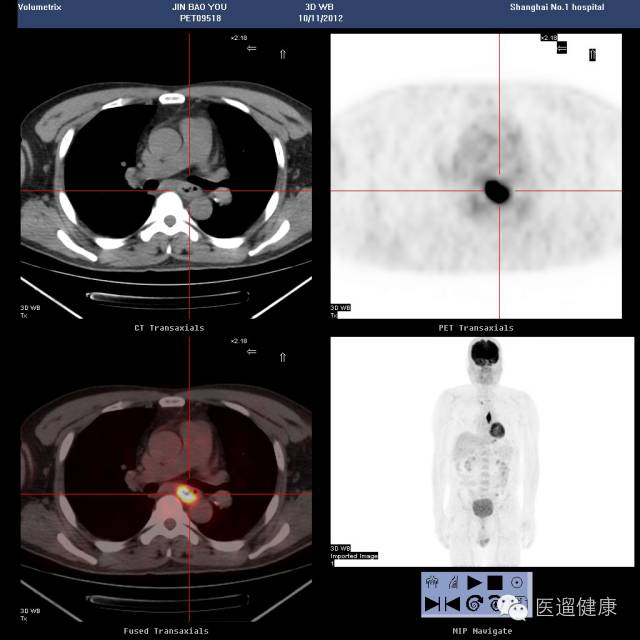

案例一、

病患:男,49岁,“吞咽困难2月余”,做了胃镜后发现食管病变。医生通过PET/CT对其食管病灶定性,了解其全身情况。

食管中段管壁不规则增厚,累及长度约5.5cm,SUV最大值22.6

我们知道SUV值越大,肿瘤的恶性程度越高。患者通过胃镜检查已经知道病变,关键是医生通过PET/CT看到了病患上纵隔有多发的淋巴结转移,肝胃韧带有多发的淋巴结转移,另外,这位病患乙状结肠上段有结节,如果只是做胸部CT的话,是不可能发现这么多的病灶的,也无法准确的分析。